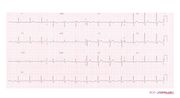

| 09:21, 9 October 2012 | Brugada ecg characteristics.png (file) |  |

39 KB | 1 | |